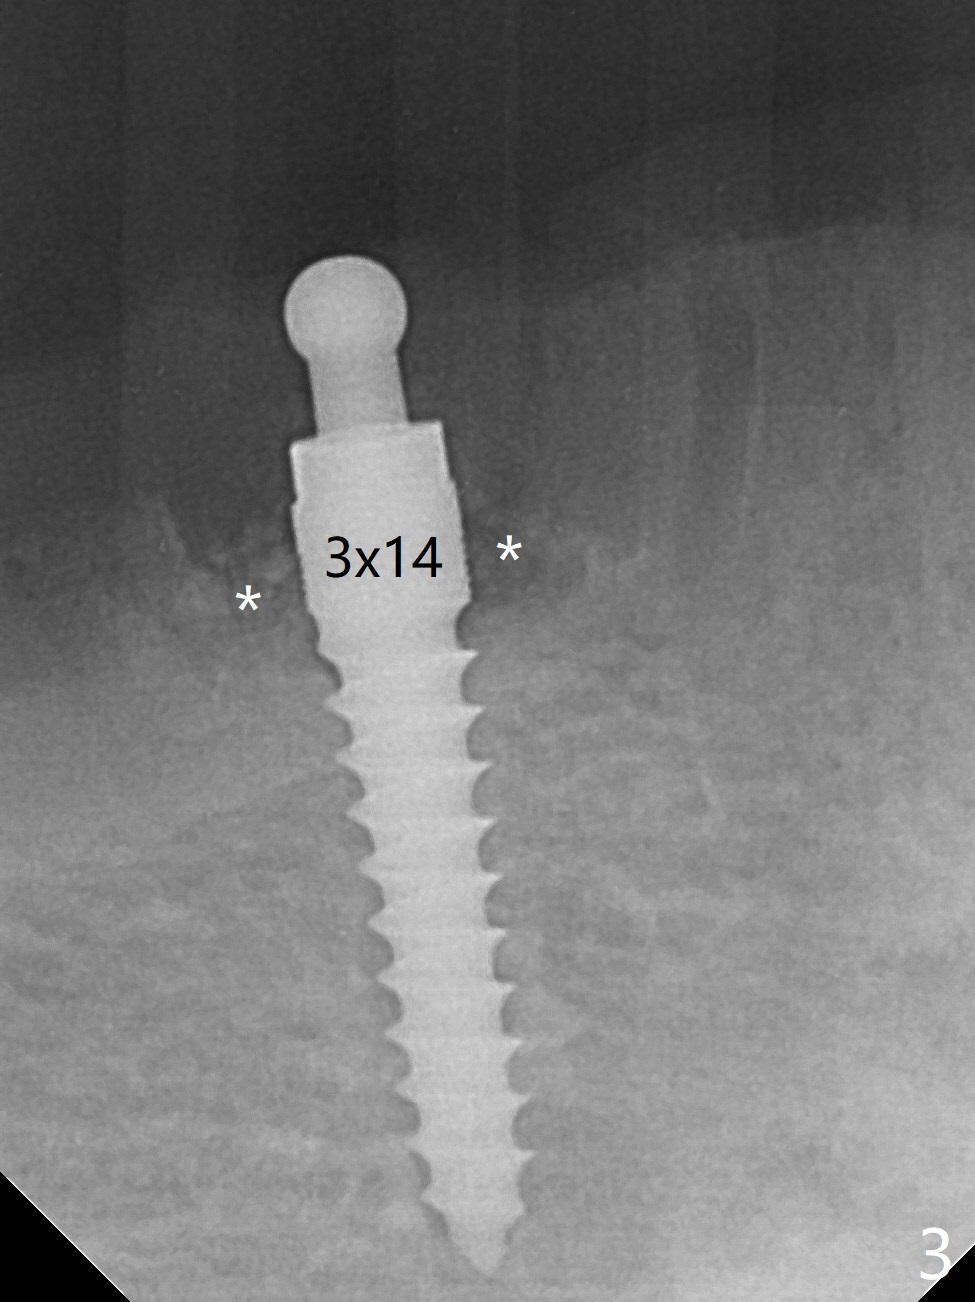

The ridge at #27 is narrow and is reduced ~ 4 mm in height (Fig.1 *) to obtain ~ 4 mm buccolingual width. A 3x14 mm 1-piece implant with ball abutment is placed (Fig.3 (*: bone graft)). In contrast, there is no problem of the buccolingual width after #22 extraction; initial osteotomy depth is 14 mm to gain ~ 5 mm of the native bone for primary stability (Fig.2). Since the lingual crest is significantly lower than the buccal one, a shorter implant (2-piece, 3.8x12 mm, Fig.4) is placed so that a ball abutment with a longer cuff is chosen (4 mm). Soft reline is applied to the site of #22 with minimal retention. But the patient is pleased with the "pain-free" procedure. It appears that gingivectomy is required for the ball abutments in 2 months (Fig.5). The implants seem osteotointegrated nearly 4 months postop (Fig.6,7). Ten months postop, the patient will return for fabrication of new full dentures to correct Class II relationship. There is mild or no bone loss 2 year 4 months postop (Fig.8,9), although the housing at #27 is dislodged. Return to Lower Canine Immediate Implant, Armaments Overdentures Xin Wei, DDS, PhD, MS 1st edition 07/24/2018, last revision 12/18/2020